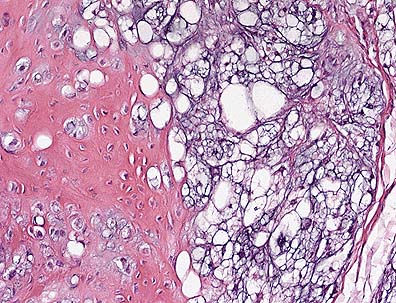

Chordoma in the tail of a ferret. Note the round to polygonal cells with abundnat clear cytoplasmic vacuoles (physaliferous cells) which are characteristic of this tumor in all species. The origin of the well-differentiated bone is yet unclear. Cartilage, not present in this field, is also seen within each lobule. (HE, 400X, 62K)

The tumor is composed of multiple lobules comprised of vacuolated cells with light pink or light blue cytoplasm. Scattered among the vacuolated cells are irregular islands of cartilage and bone. The differential diagnosis includes mucinous chondrosteoma and chordoma. Chordomas are rare in animals with the exception of mink and European ferrets. These tumors are presumed to arise from notochordal remnants.

Microscopically, chordomas of ferrets are described as infiltrative, multilobulated masses with each lobule composed of three components: closely packed vacuolated (physaliferous) cells, cartilage, and bone. The three components are often arranged concentrically, with physaliferous cells surrounding cartilage with a central core of bone. Physaliferous cells contain abundant amphophilic, foamy cytoplasm, and ahve round to oval nuclei. Mitoses are rare. The physaliferous cells are supported by a mucinous matrix of variable thickness that blends gradually with mature cartilage and bone. The bone often contains marrow. Immunohistochemically, physaliferous cells stain strongly positive for both vimentin and keratin, and weakly positive for S-100 protein and neuron specific enolase. Only in ferrets do chordomas contain bone.